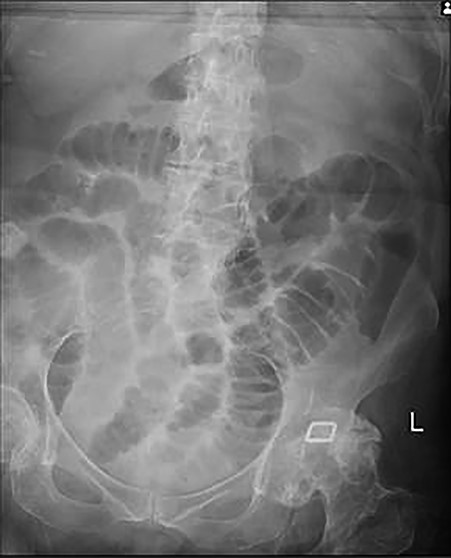

As the gallstone was seen within the ascending colon, the patient was managed conservatively for 2 days after which she was able to tolerate fluids then light diet. Follow-up abdominal X-ray revealed that the gallstone had reached the rectum with no radiological signs of bowel obstruction (Fig. 3). On the fourth day of admission, she opened her bowels and abdominal distension completely resolved.

Follow-up abdominal X-ray revealed the gallstone in the rectum and that bowel obstruction has now resolved.